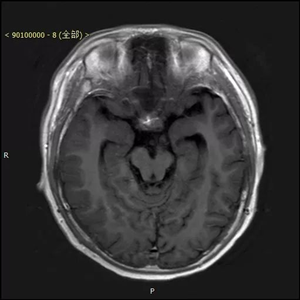

患者,男,入院时间2016年8月9日,入院时年龄13岁5月24天。主诉:右腿晃动3个月,伴右侧肢体力量减弱2个月。术后病理显示为囊性成熟型畸胎瘤,肿瘤组织内神经胶质细胞成分、平滑肌及腺上皮成分细胞异质性明显。

患者来到北京儿童医院就医时,由于肿瘤压迫脑功能区导致了瘫痪。北京儿童医院神经外科葛明教授及团队,对其进行了全切除手术,肿瘤直径4公分左右,手术路径深十公分左右,分块切除,历时四小时完整切除。术后患者瘫痪状态消失,随访恢复良好。

患者术前资料(下图)

患者术后资料(下图)